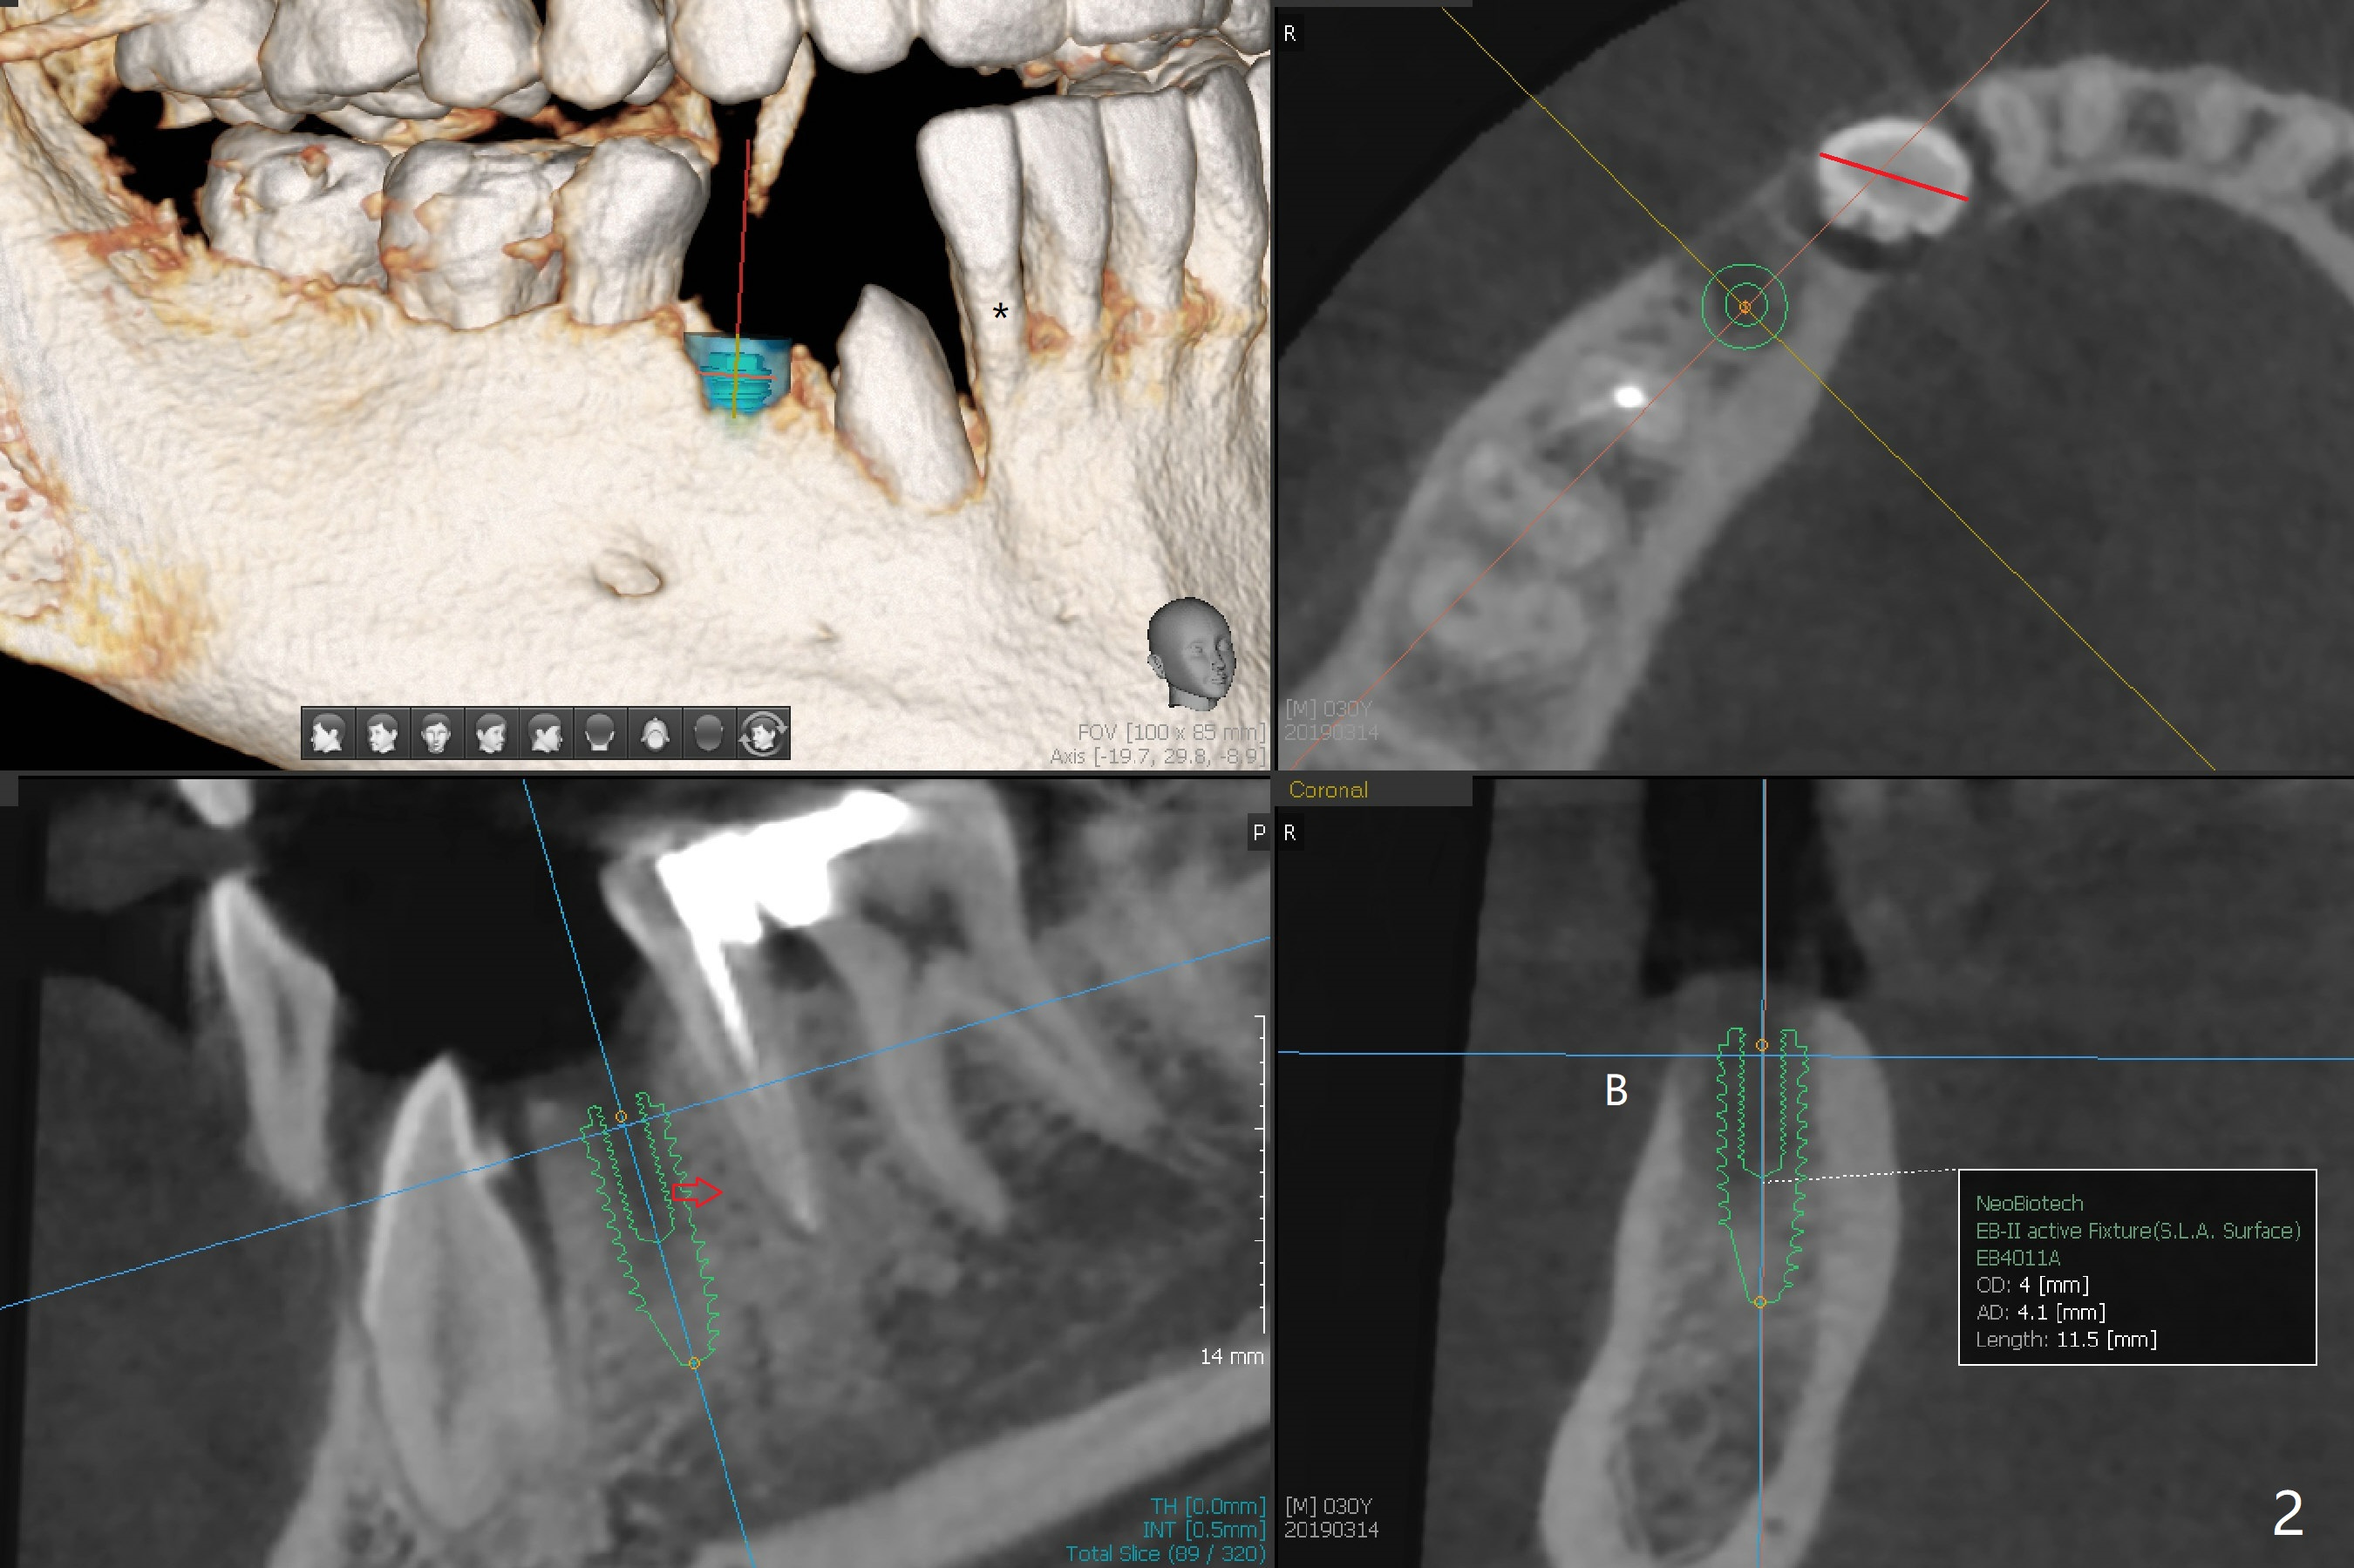

A 30-year-old man requests orthodontic extrusion of the impacted lower right canine and implant at the next site (Fig.1). Since the canine rotates with wider mesiodistal width of the crown (Fig.2 red line), the implant should be smaller and placed distal (Fig.2 red arrow). The extrusion will gain the bone to the distal surface of the lateral incisor (Fig.2, 3*). In fact the tooth #27 is malformed in that the root is split (Fig.4, as compared to the tooth #22 (Fig.5)). Surgical guide will be used for precision.